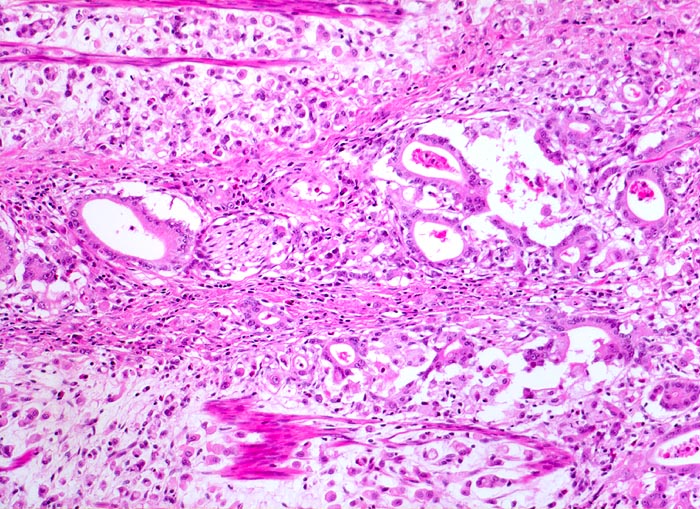

PathoPic – image database / PathoPic ID 3385 - Adenokarzinom des Magens mit Siegelringzellen

Adenokarzinom des Magens mit Siegelringzellen

maligner Tumor

Magen

Beschreibung

Diffuse Verdickung und Versteifung der Magenwand im Sinne einer Linitis plastica bei intakter Schleimhautoberfläche. Aufhebung des Faltenreliefs.

Seit einigen Monaten klagte der Patient über unspezifische Oberbauchbeschwerden.

Der histologische Subtyp eines Siegelringzellkarzinoms darf dann diagnostiziert werden, wenn die Siegelringzellen mindestens 50% der Tumormasse ausmachen.

Histologie

100